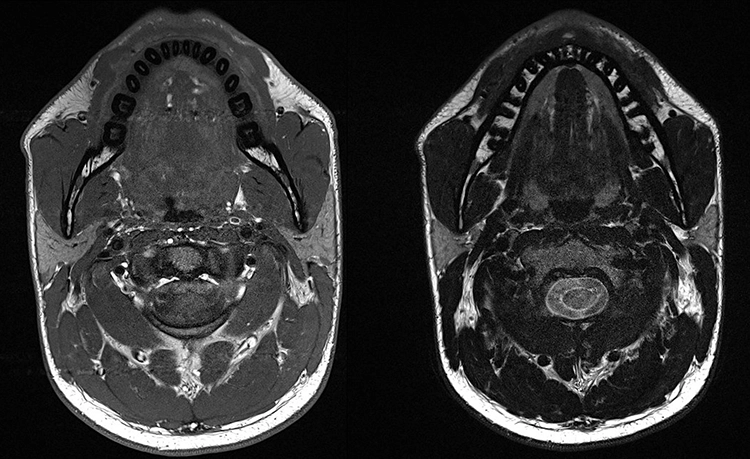

Die Magnetresonanztomographie (MRT) ist in der Medizin seit vielen Jahren etabliert und erobert dort mit unzähligen, jährlich zunehmenden Optionen und Sequenzen immer weitere Anwendungen. Damit übertrifft die MRT in der Medizin deutlich alle anderen In-vivo-Bildgebungsarten im menschlichen Körper ohne invasive Eingriffe und ionisierende Strahlung [7]. Aufgrund neuer hardware- und softwareseitiger Entwicklungen ist sie im letzten Jahrzehnt auch zunehmend für Anwendungen in der Zahn-, Mund- und Kieferheilkunde interessant geworden [8] (Abb. 3).

Im Jahr 2023 stellte Siemens in Kooperation mit Sirona ein Projekt für ein „dental dedicated MRT“ vor, bei dem ein speziell für die zahnmedizinischen Anforderungen maßgeschneidertes MRT entwickelt und auf den Markt gebracht werden soll.** Hier spielen die neuen technischen Möglichkeiten in der möglichen Größenreduktion und auch in reduzierten hardwareseitigen Anforderungen eine Rolle. Eine Arbeitsgruppe aus Aarhus betreibt bereits ein prototypisches Gerät [10]. Einige Aufnahmen dieses Prototyps sind in den Abbildungen 4 und 5 zu sehen. Das Gerät wurde auf der Konferenz der European Academy of Dentomaxillofacial Radiology (EADMFR) vom 12. bis 15. Juni 2024 offiziell vorgestellt.***